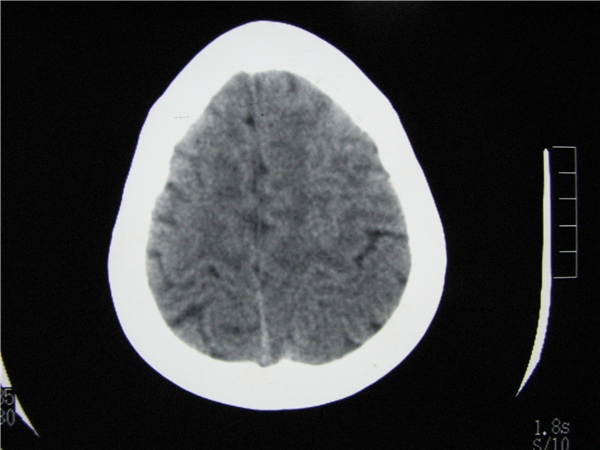

m 15y 头痛,以前有外伤史请老师看看除了囊肿还有别的吗?

蛛网膜囊肿。眼拙,看不出别的,倒是看到了双侧大脑中动脉影,类似“致密动脉征”。

双侧侧裂池和纵裂池近前颅窝蛛网膜囊肿。

无明显占位及负占位效应,考虑软化灶并脑室穿通畸形囊肿、局限性脑萎缩

蛛网膜囊肿,不能除外脑穿通畸形,支持。